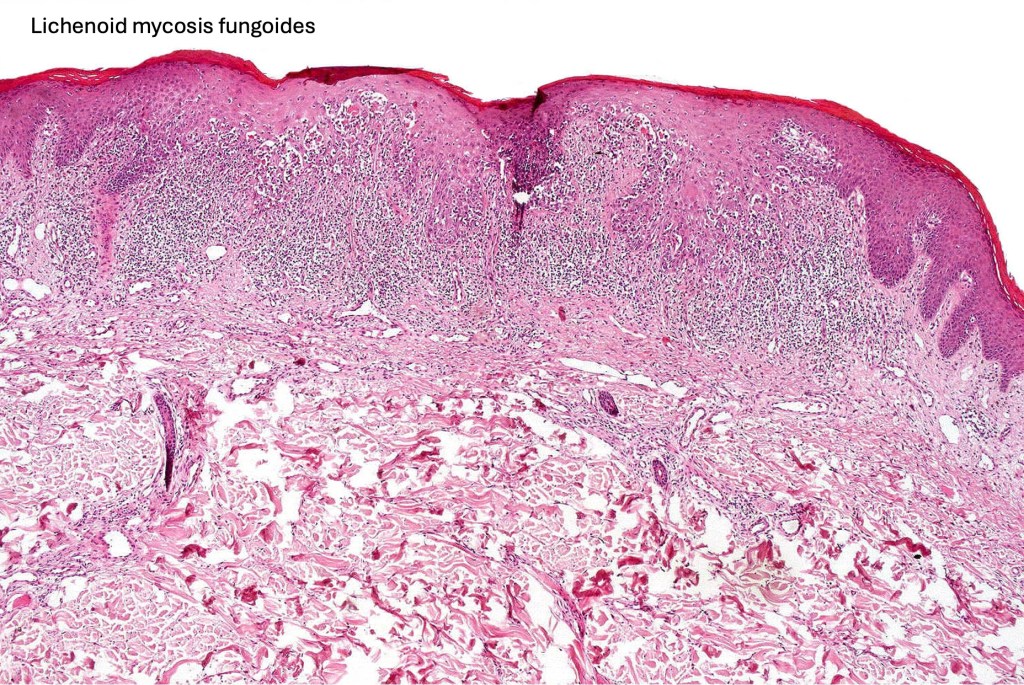

Histological features

The histological hallmark of mycosis fungoides is the presence of large atypical lymphocytes with a convoluted/cerebriform nuclear border (Sézary cells). These may be found at the epidermal-dermal jnuction and as collections within the epidermis (Pautrier microabscess). These are most easily found in plaque stage disease. The epidermal component can be subtle in patch stage disease and is often lost in tumor stage dsease. The classification into patch, plaque & tumor stage disease is less helpful histologically as the features merge from one to the other. It is all a matter of degree.

Plaque Stage Disease

•Compact hyperkeratosis & patchy parakeratosis

•Acanthosis

•Psoriasiform hyperplasia common

•Epidermotropism is often marked with conspicuous Pautrier microabscesses

•Lichenoid variant & poikiloderma atrophicans vasculare

•Variable folliculotropism (+/- mucinosis) & syringotropism

•Coarse collagen bundles in papillary dermis

•Superficial band-like dermal infiltrate of atypical lymphocytes, eosinophils, plasma cells & histiocytes